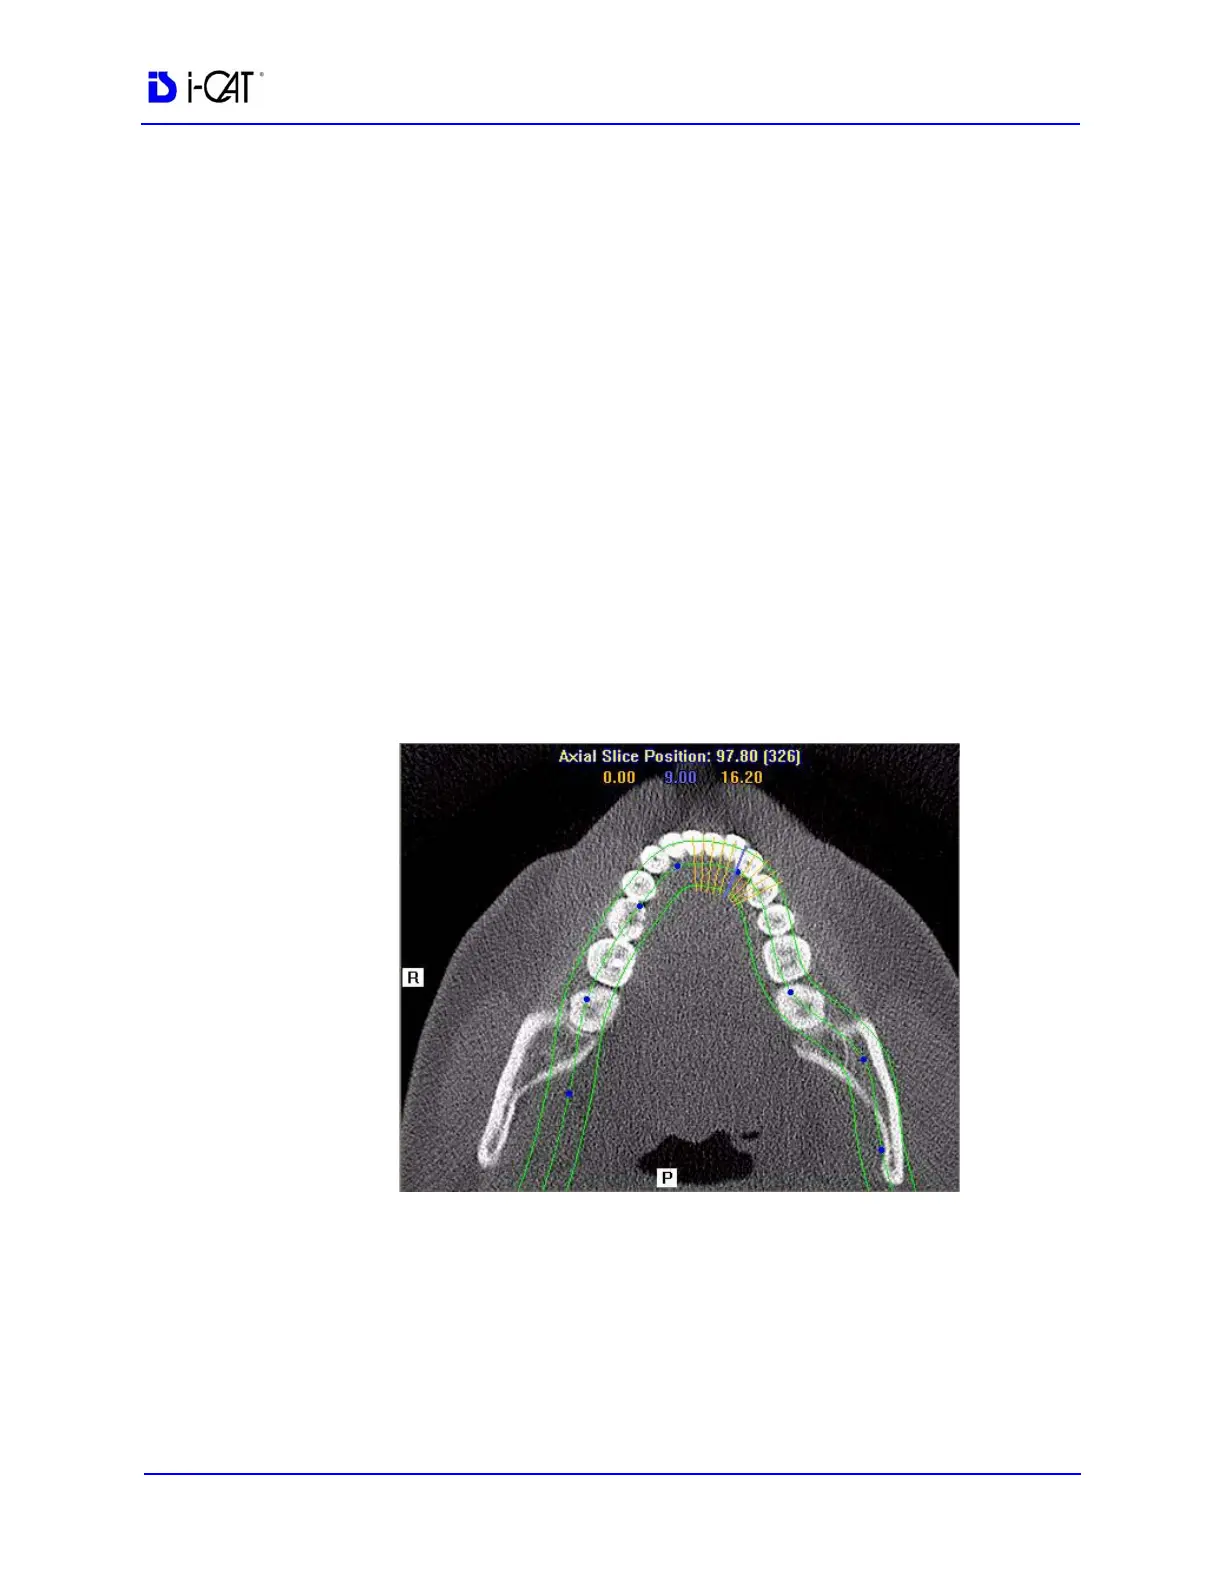

Cross Section Views (lower right) shows cross section

details of the anatomy of interest as specified on the axial

slice position view and the panoramic map view. The mouse

scroll wheel is active to scroll through the slices.

Patient position indicators are used on the Implant Planning Screen

to indicate the orientation of the displayed data. These are:

R = Right Side

P = Posterior

B = Buccal

1. Click and drag the blue dots on the axial slice position view to

adjust the image displayed on the panoramic map view.

To correlate the mouse position on the axial slice position view to

the panoramic map view, hold down the C key on keyboard and

move the mouse. A yellow mark shows the correlated position.